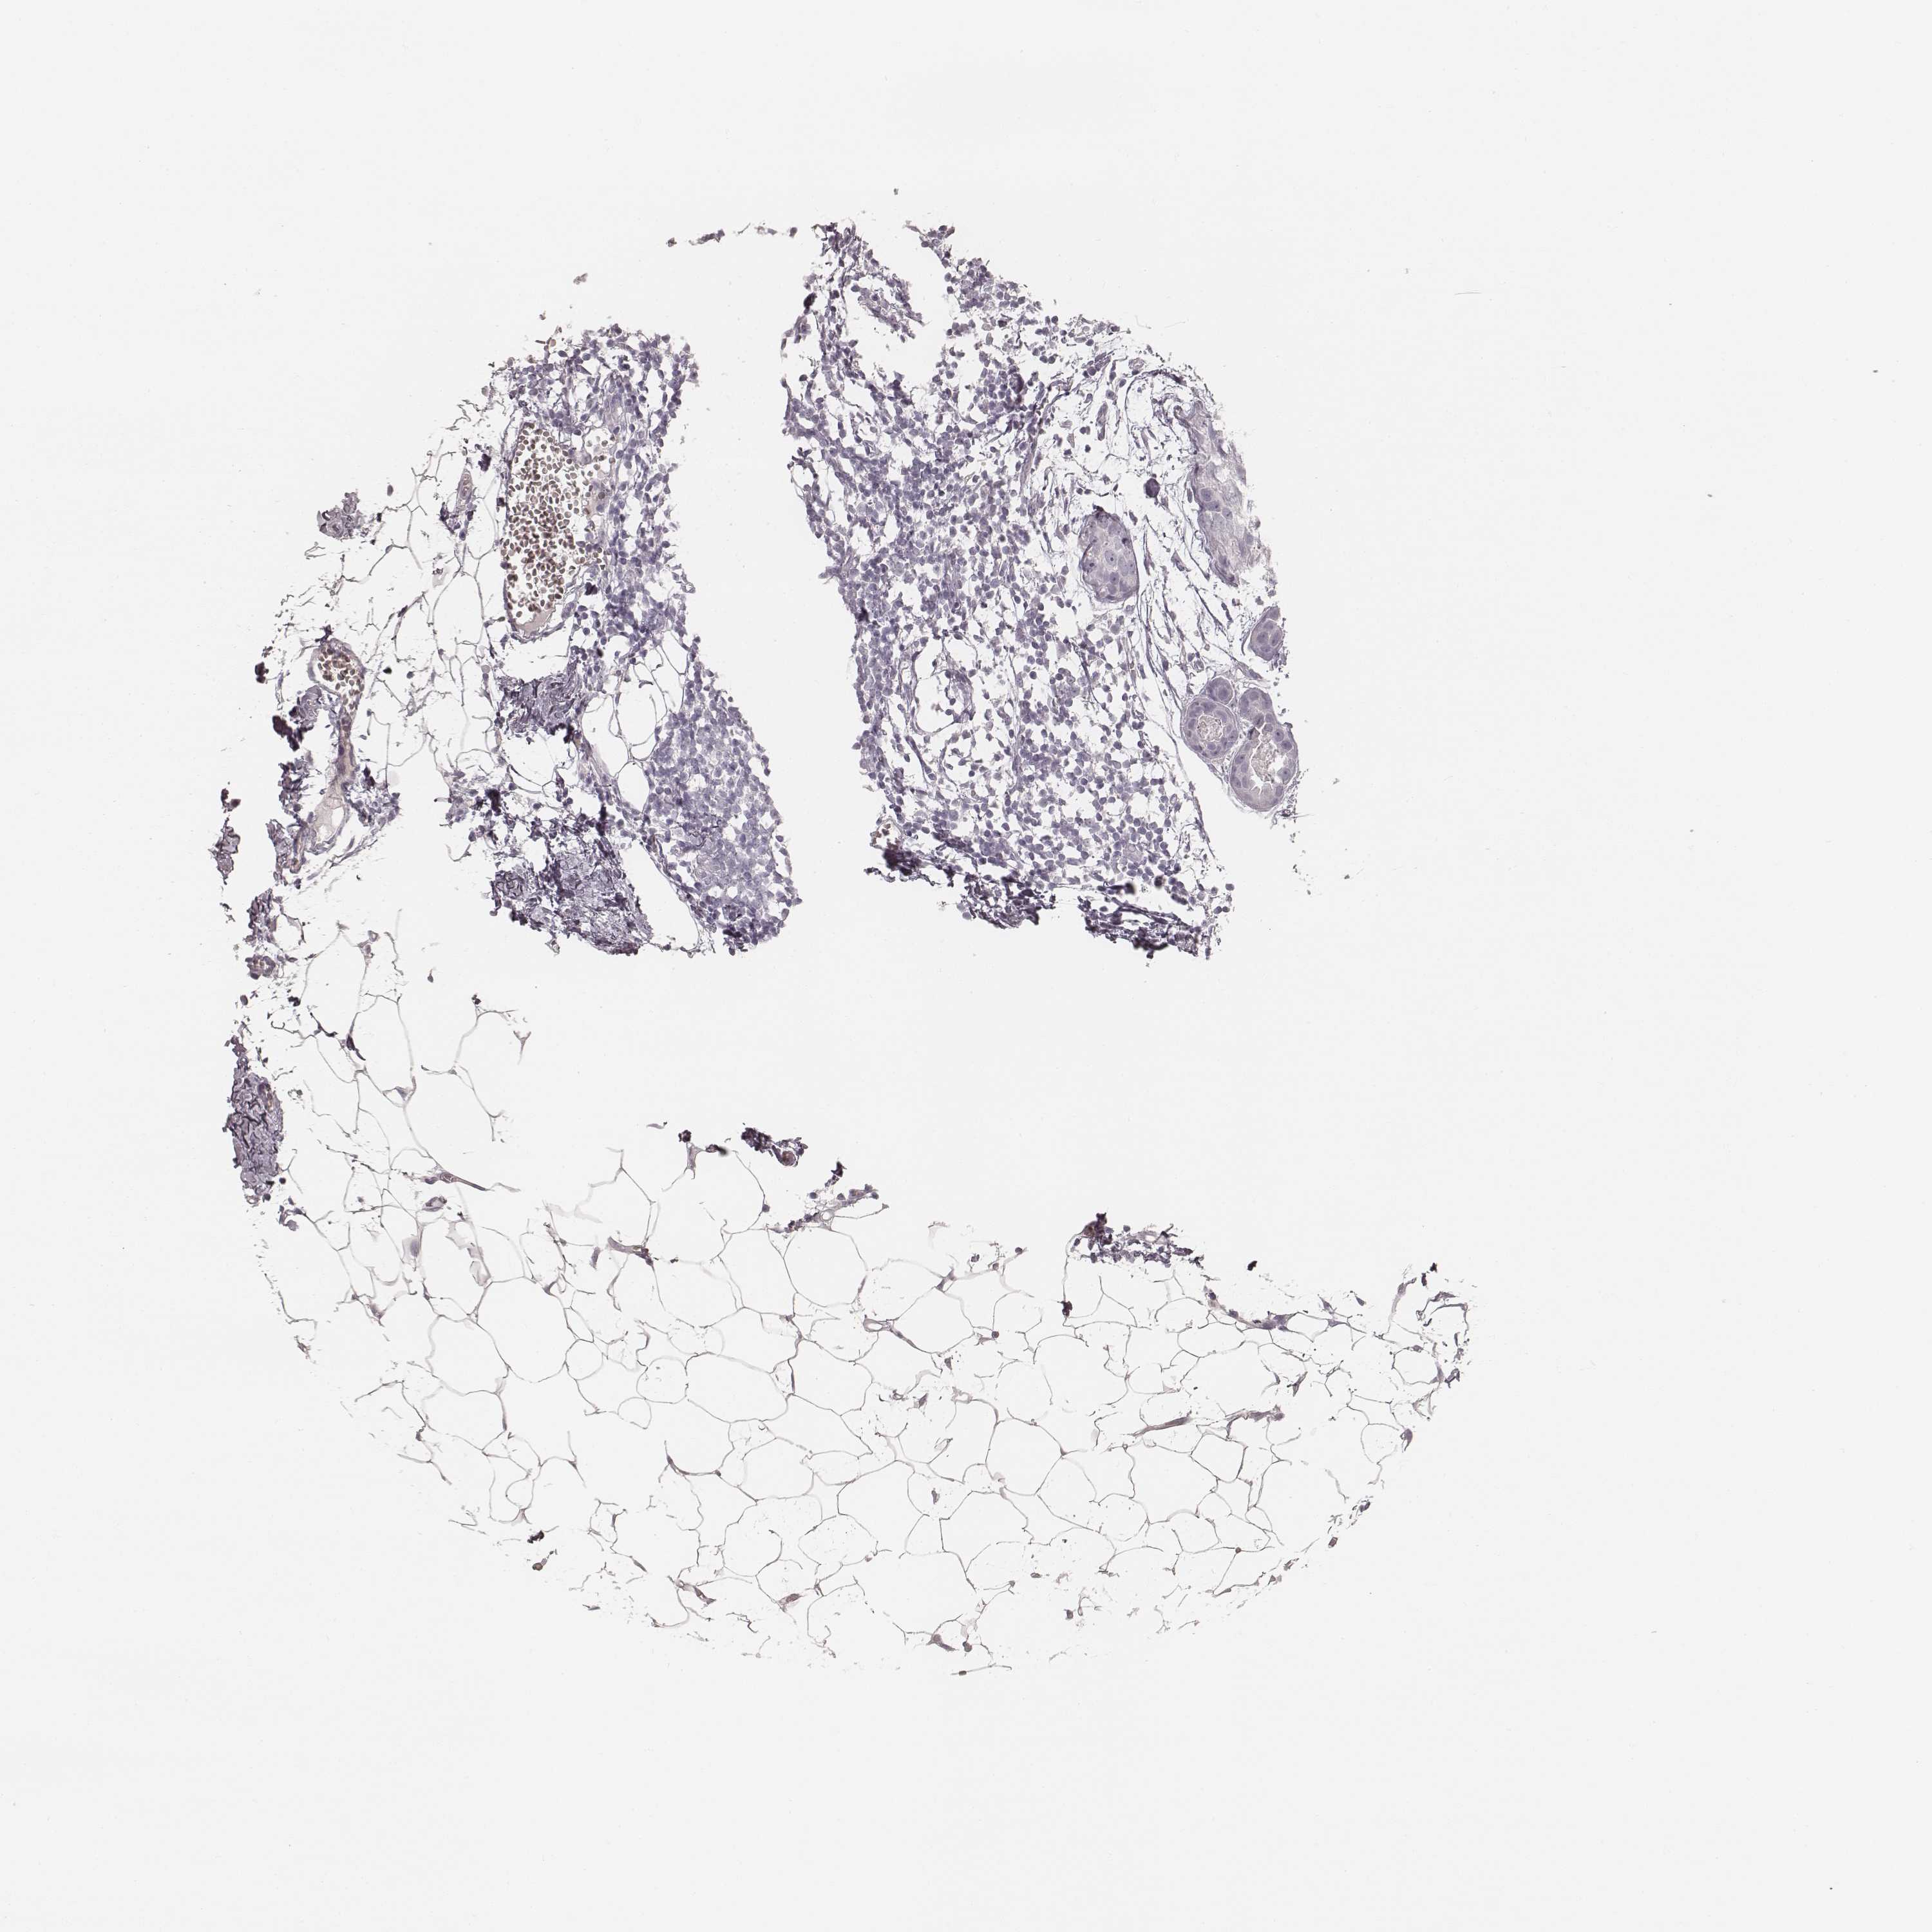

CANCER BREAST CANCER Show tissue menu

Breast cancer

Human cancer